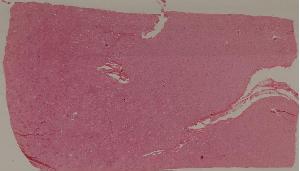

74.新月体性肾炎